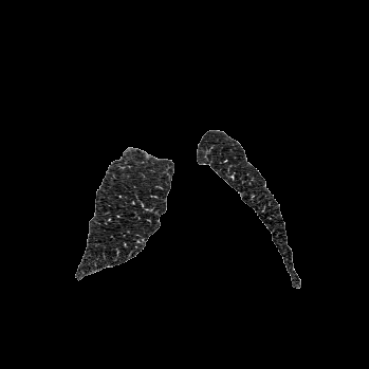

Inverse consistent rigid, affine, nonparametric, and MLP registration. We train networks on MNIST 5s using the methods in Secs. 3 and 4, demonstrating that the resulting networks are inverse-consistent. Our TwoStepConsistent (TSC) operator can be used on any combination of the networks defined in Sec. 3. For demonstrations, we join an MLP registration network to a vector field registration network, and join two affine networks to two vector field networks. Fig. 2 shows successful inverse-consistent sample registrations.

OAI Knee MRI We train and test on the split published with [22], with 2532 training examples and 301 test pairs from the Osteoarthritis Initiative (OAI) [16]444https://nda.nih.gov/oai. We evaluate using the mean Dice score of tibial and fibial cartilage. To compare directly to [22, 7, 23] we train and evaluate at [80x192x192].

| Moving Image | Warped Image | Fixed Image | Moving Image | Warped Image | Fixed Image |